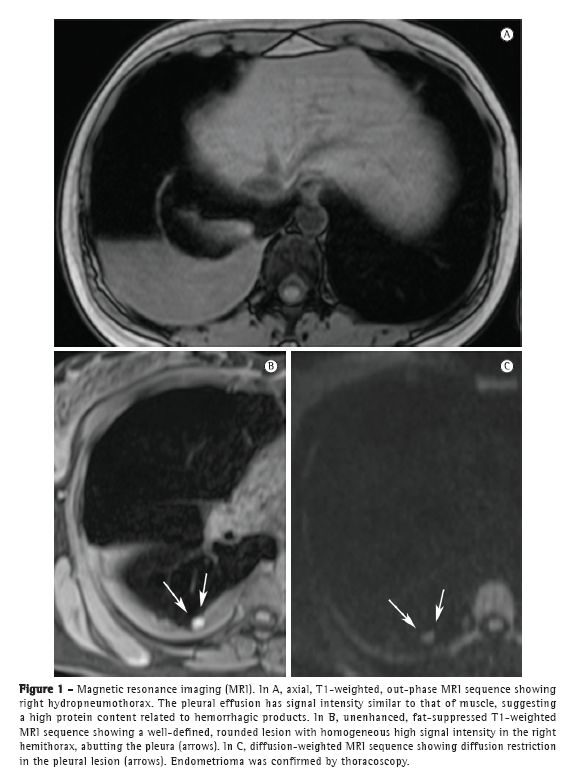

The patient remained asymptomatic for 4 years. Approximately six months prior to this writing, the patient presented with cyclic dyspnea, dry cough, and mild pelvic pain, despite her use of oral contraceptives. A chest X-ray and a CT scan of the chest revealed mild right hydropneumothorax. The lung parenchyma was normal. On T1- and T2-weighted MRI sequences of the chest, performed with and without fat suppression, we observed right hydropneumothorax, and T1-weighted MRI sequences with fat suppression showed hyperintense nodular lesions in the pleura; some of those lesions showed restricted diffusion (Figure 1), which is suggestive of endometriomas.

In recent years, MRI of the chest has progressed markedly. Because of improvements in speed and image quality, MRI is now ready for routine clinical use.(7-9) In both of the cases presented here, chest MRI revealed hydropneumothorax and well-defined, rounded nodules on the pleural surface in the right hemithorax. In Case 1, the pleural effusion had intermediate signal intensity on T1-weighted images, suggesting high protein content, probably related to hemorrhagic products. In Case 2, the pleural effusion had high signal intensity, suggesting recent hemothorax. The pleural nodules observed in Case 1 showed homogeneously high signal intensity on fat-suppressed T1-weighted images and restricted diffusion on diffusion-weighted imaging (DWI). In Case 2, the nodules showed heterogeneous signal intensity on T1- and T2-weighted images, without diffusion restriction. As in pelvic endometriosis,(1,10) pleural nodules of thoracic endometriosis might show different signal intensity on T1- and T2-weighted images, as well as variable diffusion restriction, depending on the age of the lesion.